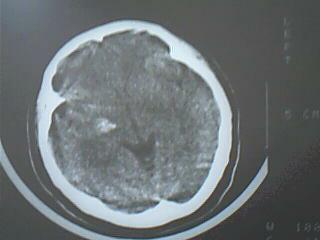

以下是引用liyf在2008-8-14 20:00:00的发言:[br]右侧基底节区脑出血。